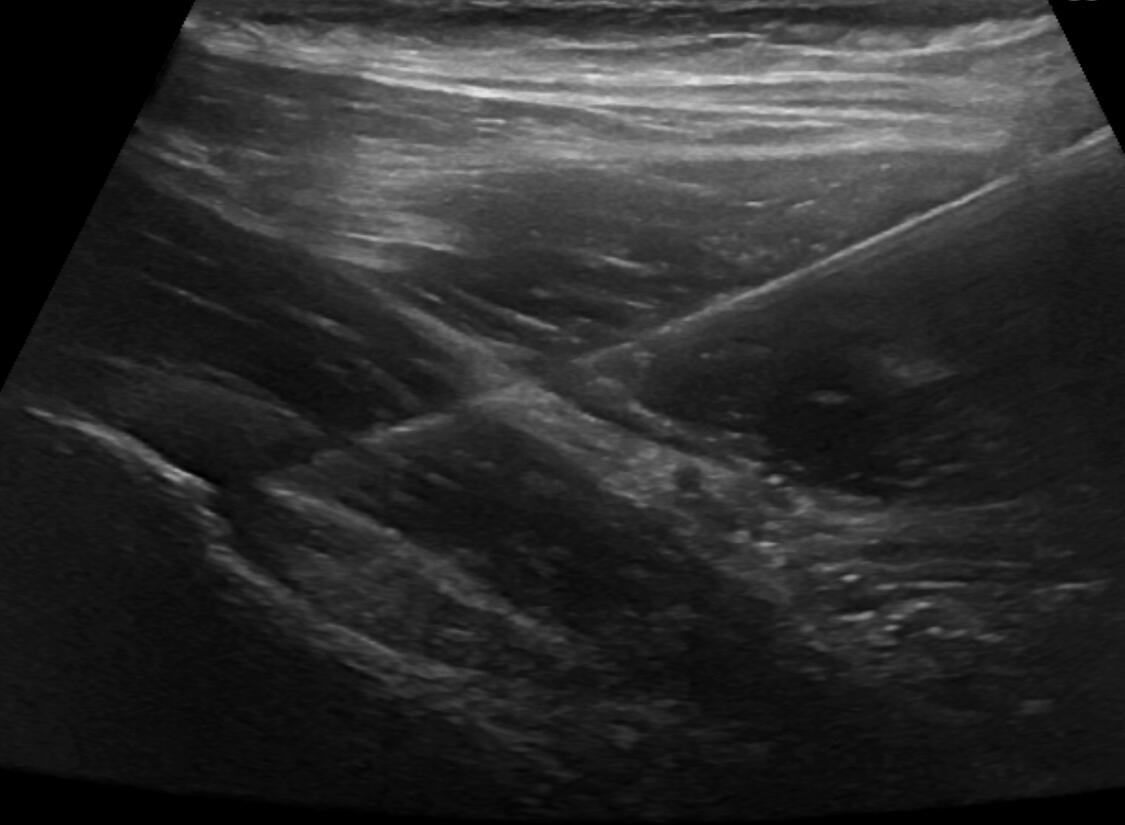

Hip joint injection (ultrasound guided)